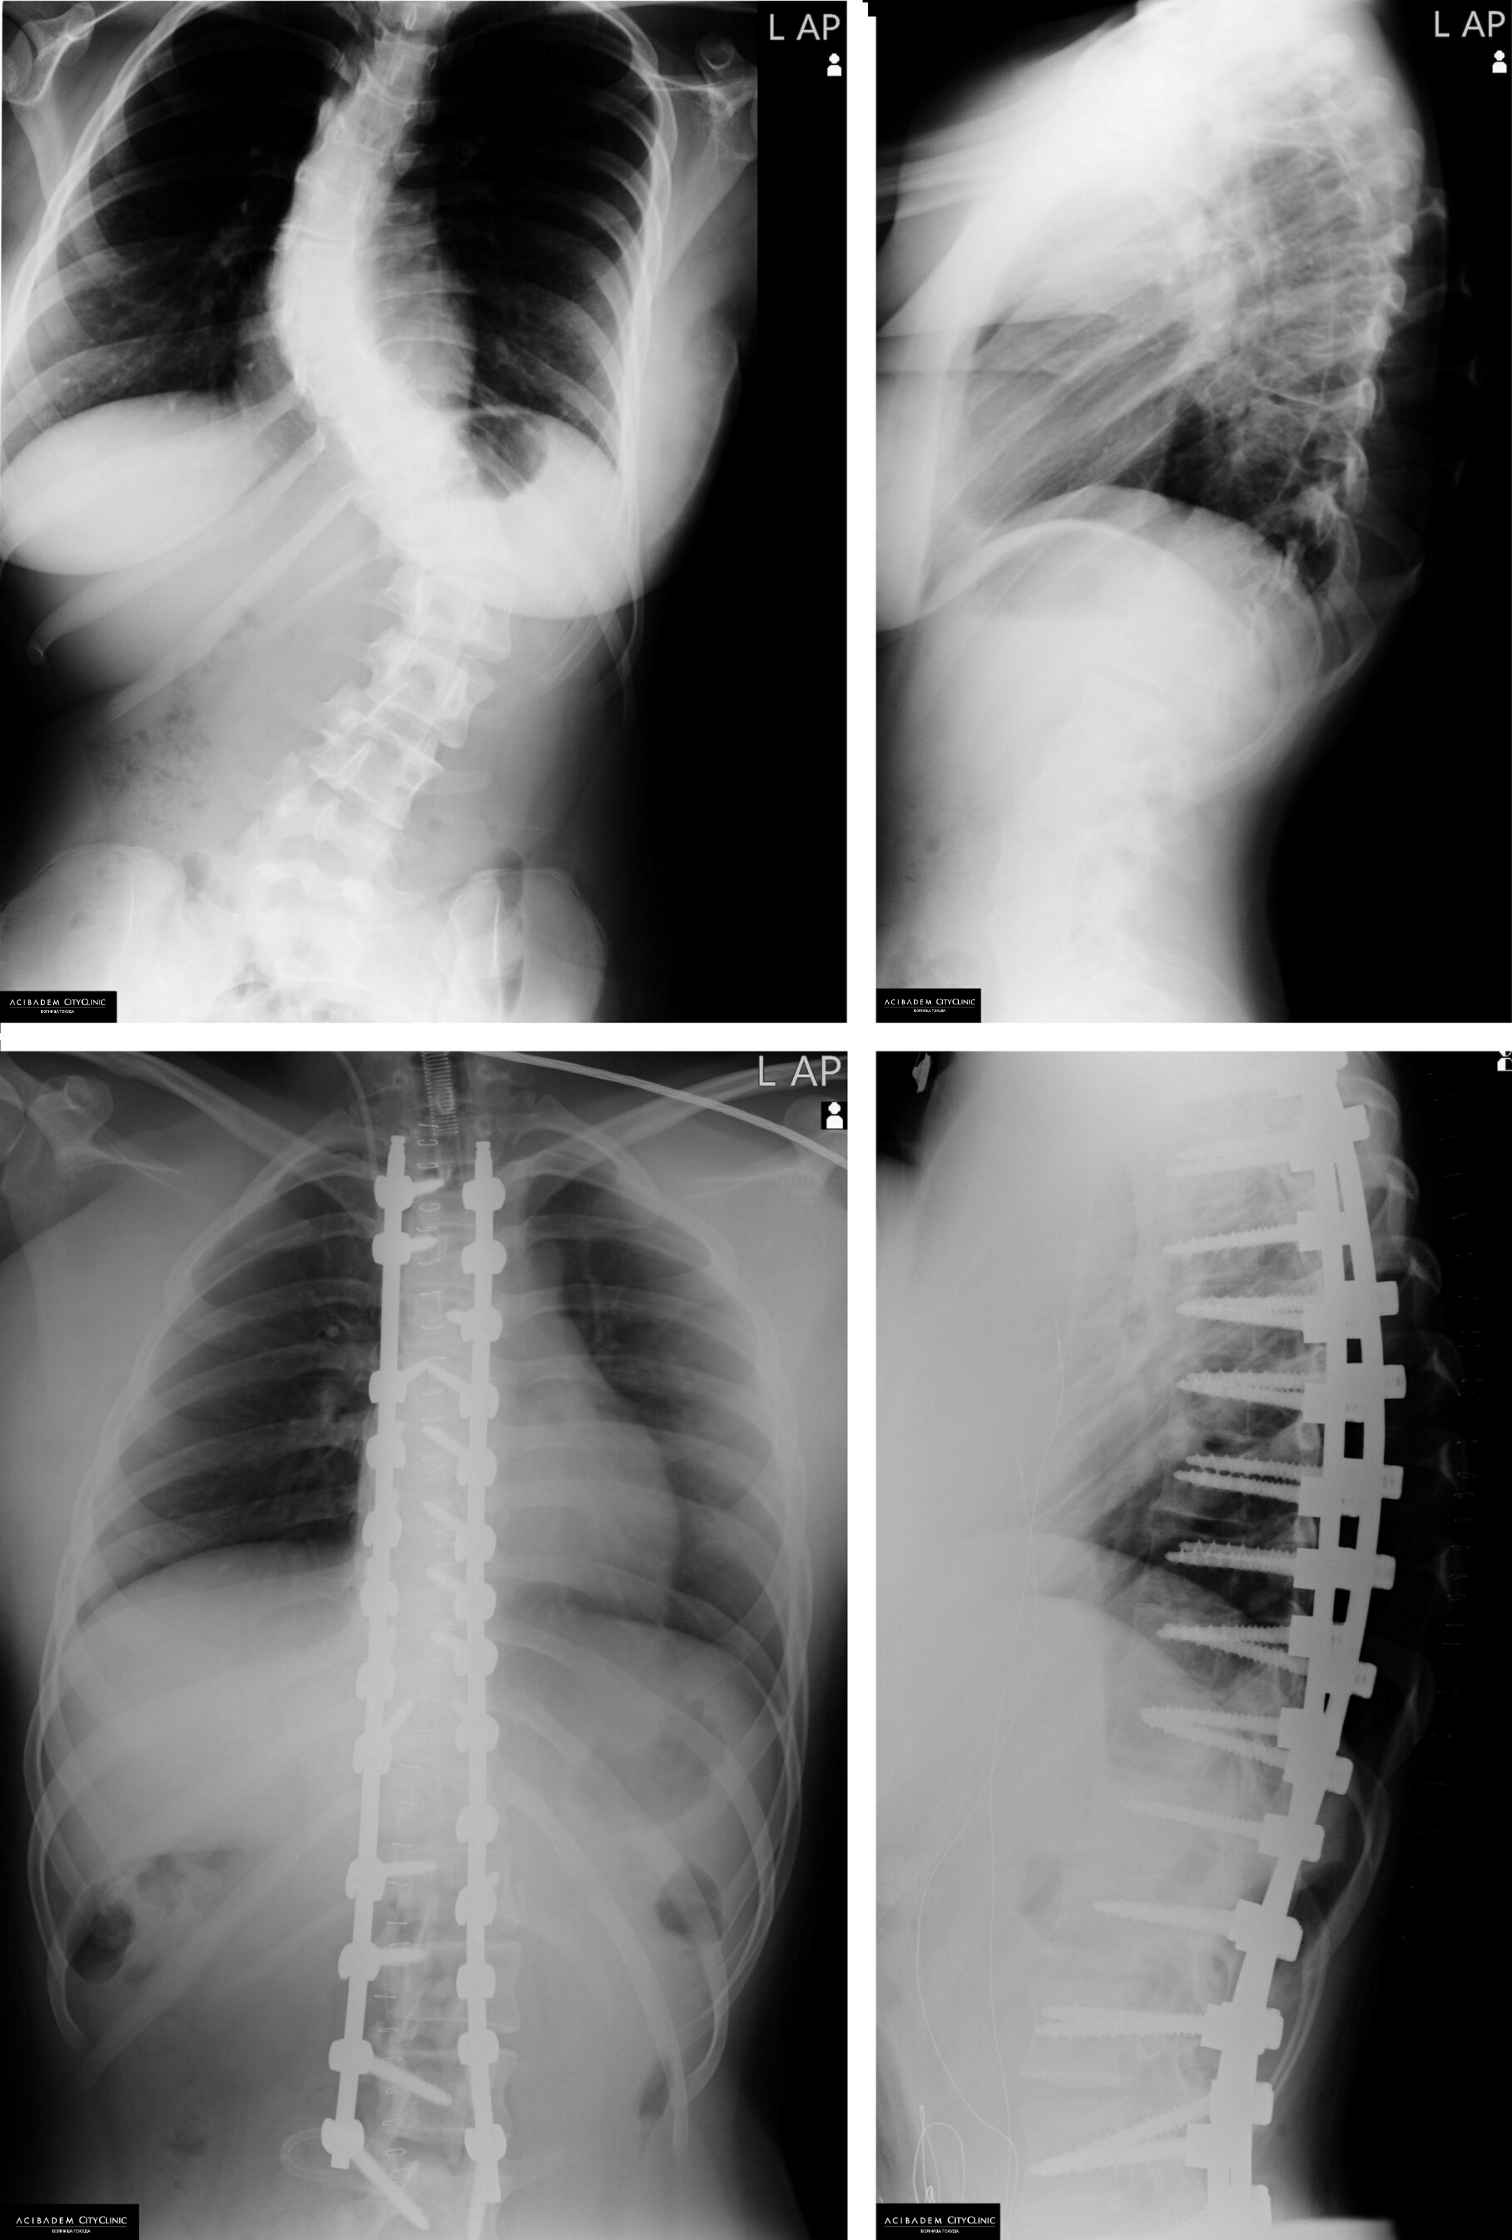

Сколиозата е деформация на гръбначния стълб, което се среща най-често при деца в подрастваща възраст, по-често при момичетата. Представлява странично изкривяване във фронталната равнина, което може да бъде с една или няколко кривини в различни сегменти от гръбначния стълб. Има няколко категории сколиоза, но най-често срещаната е идиопатичната адолесцентна сколиоза. Тя засяга деца в юношеска възраст (от около 10 до 18-20 г.) и при нея причините са неизяснени. Според тежестта на гръбначната деформация е необходимо да бъдат взети мерки със съответната препоръчителна терапия - носене на корсет, кинезитерапия или хирургия при много тежките случаи.

Наблюдението на детето е изключително важно от страна на родителите, които при забелязване и съмнение за проблем, е добре да проведат консултация с ортопед. Има случаи на бързо прогресиране на изкривяването до степен, в която се увреждат вътрешните органи. Това не само пречи на естетическия вид на детето, влошава качеството му на живот, но създава и опасност за здравето му. В тези случаи хирургията остава последният вариант за лечение.

В Клиниката по Ортопедия и травматология в Болница Токуда от дълги години има изграден център за лечение на сколиоза. Ние сме водещ център, където се прилага съвременна хирургия при сложни случаи на гръбначни изкривявания.

Екипът, воден от доц. д-р Васил Яблански и подпомаган през годините от американски хирурзи от Обществото за изследване на сколиозата, оперира по най-съвременните методи средно по 30 деца с тежка сколиоза всяка година. В болницата е създадена и програма за неинвазивно кинезитерапевтично лечение по световноизвестния Шрот метод.